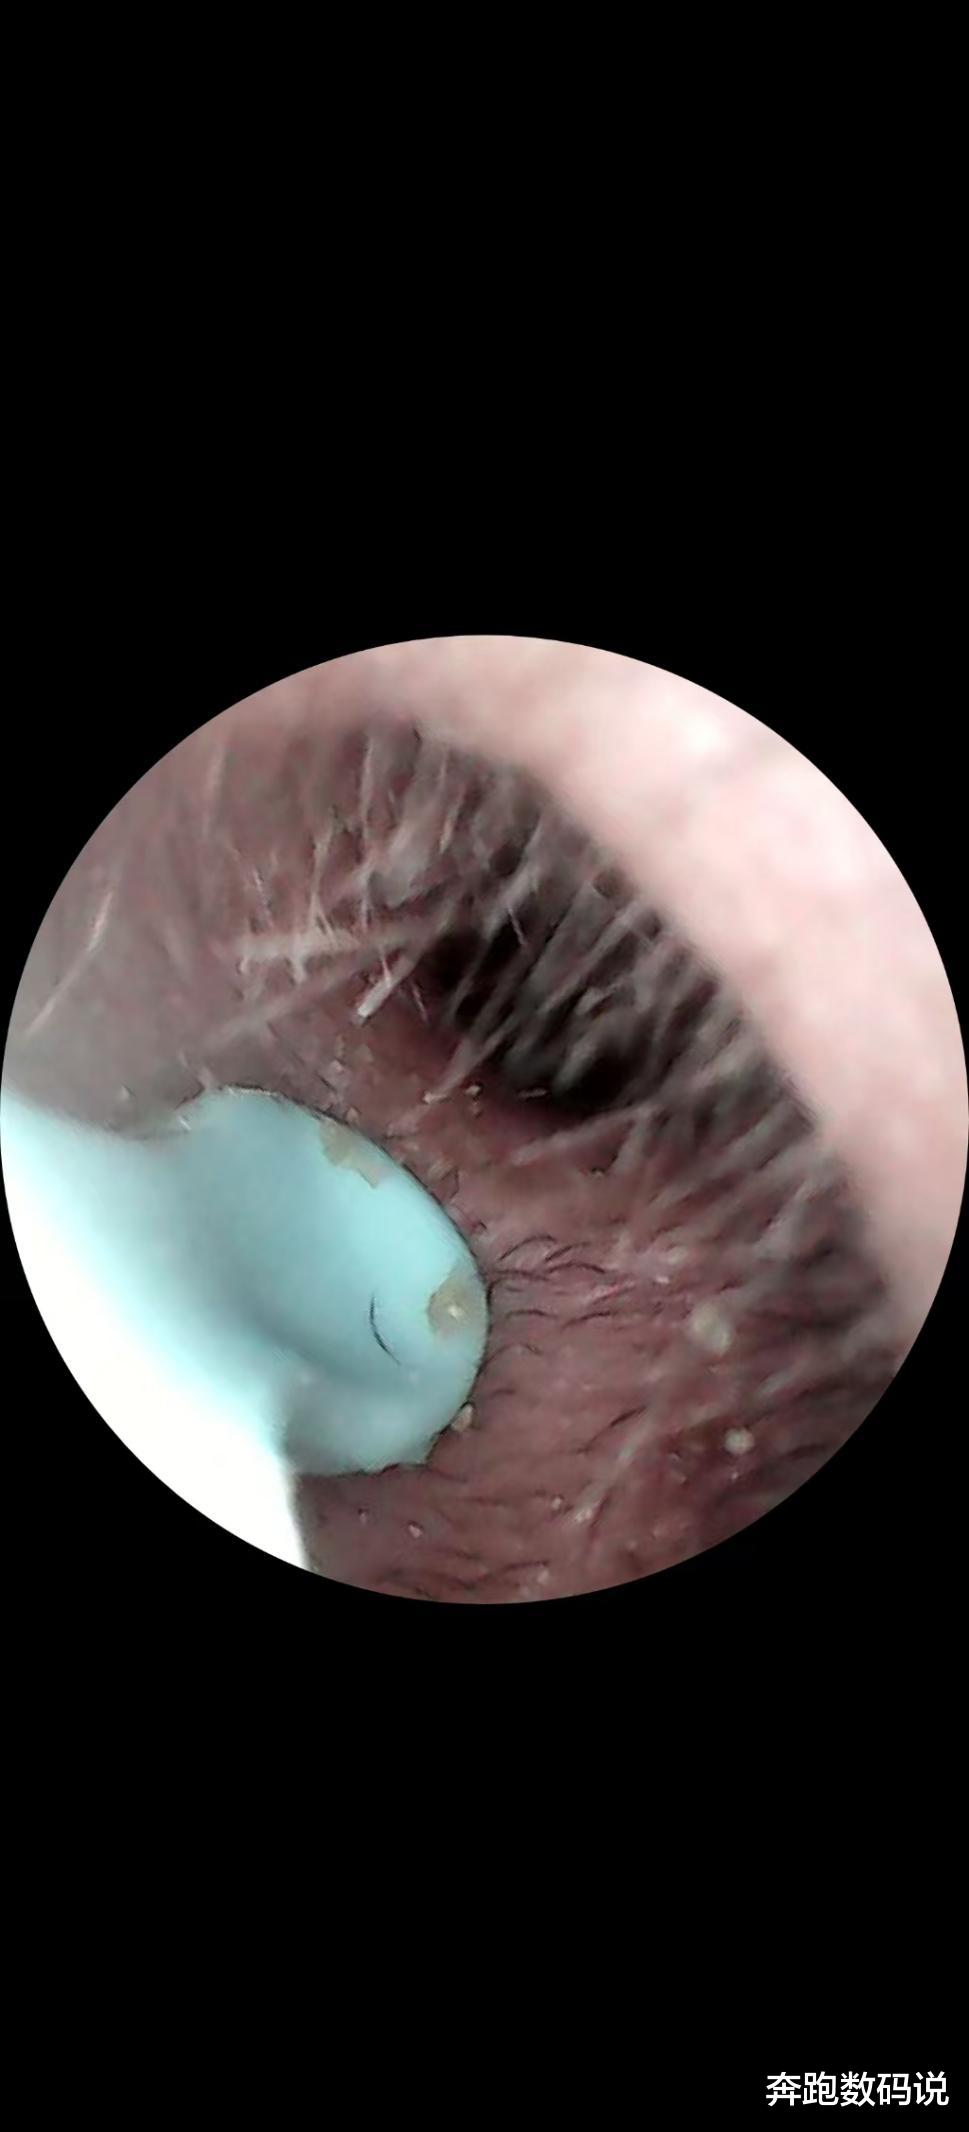

作为一款智能可视耳勺,成像清晰度是关键。西圣 Find X 搭载 1500 万像素高清镜头,配合 F2.0 大光圈与多层光学镀膜镜组,实际体验中,耳道内的每一处细节都清晰呈现。

无论是细微的绒毛、耳道壁的纹理,还是深藏的耳垢,都能看得一清二楚,画质直逼专业内窥镜。初次通过手机 APP 看到自己耳道内部时,那种震撼感难以言表,仿佛打开了一个全新的微观世界。